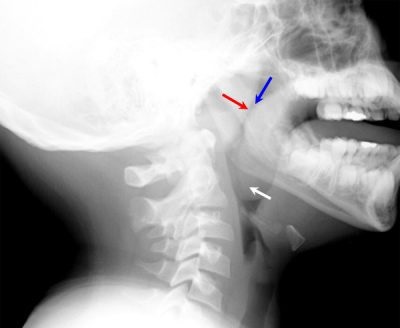

kutatási módszerek

Ahhoz, hogy értékeli a nazofaringeális mandulában, alakja, mérete és a jelenléte a kóros folyamat, az ilyen technikákat használjuk:

Ez a módszer lehetővé teszi, hogy értékelje a feltétele a mandulák, a nagyítás mértéke határozza meg a nyálka jelenlétének vagy bőrvörösség. Ellenőrzés egy tükör segítségével a fő végleges diagnózist „orrpolip”, de más módszerek is alkalmazhatók megerősítést. A vizsgálat során, az egyik csak emelkedik a szövetekben, és az bőrpír.

A gyulladás okozta megfázás, a becslések szerint orrpolip, bár az arány a test jön pár napon belül talpra a hideg. Eljárás lefolytatását okoz minimális kényelmetlenséget, hogy a gyermek számára.